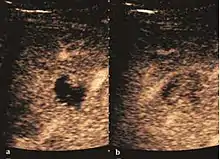

Hepatic hemangioma (CEUS). Progression of CA from the periphery toward the center of the lesion is evidenced by examination at various time intervals (a – arterial phase; b – late phase).

It is the most common liver tumor with a prevalence of 0.4 – 7.4%. It is generally asymptomatic but also can be associated with pain complaints or cytopenia and/or anemia when it is very bulky. It is unique or paucilocular. It can be associated with other types of benign liver tumors. Characteristic 2D ultrasound appearance is that of a very well defined lesion, with sizes of 2–3 cm or less, showing increased echogenity and, when located in contact with the diaphragm, a "mirror image" phenomenon can be seen. When palpating the liver with the transducer the hemangioma is compressible sending reverberations backwards. Doppler exploration reveals no circulatory signal due to very slow flow speed. CEUS investigation has real diagnosis value due to the typical behavior of progressive CA enhancement of the tumor from the periphery towards the center. The enhancement is slow, during several minutes, depending on the size of hemangioma and on the presence (or absence) of internal thrombosis. During late (sinusoidal) phase, if totally "filled" with CA, hemangioma appears isoechoic to the liver. Deviations from the above described behavior can occur in arterialized hemangiomas or those containing arterio-venous shunts. In these cases, differentiation from a malignant tumor is difficult and requires other imaging procedures, follow up and measurements of the tumor at short time intervals.[4]